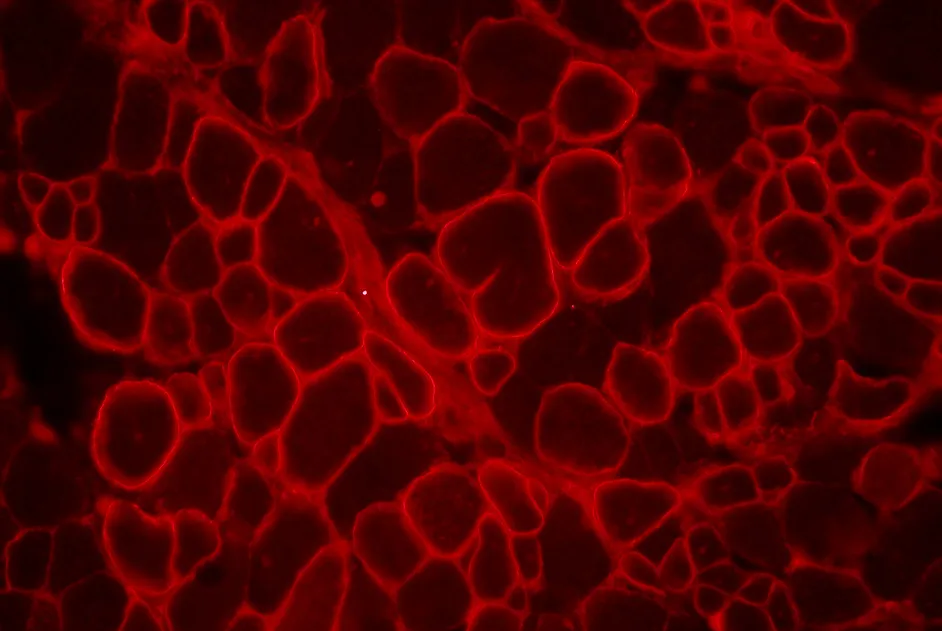

Les auteurs observent une restauration partielle de l’expression de la dysferline dans les fibres musculaires. De plus, des fibres isolées des muscles traités sont capables de réparer leur membrane après lésions, traduisant une restauration de la dysferline fonctionnelle dans les fibres musculaires.